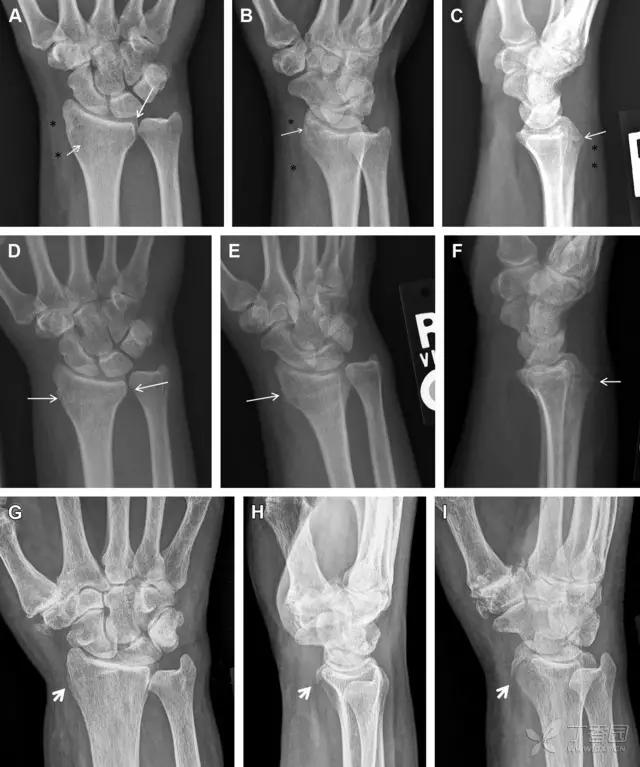

30 桡骨远端骨折

常规进行前后位、侧位、斜位 X 线检查,对于大多数桡骨远端骨折来说不容易漏诊;但是对于无移位的骨折,特别是桡骨茎突骨折,容易漏诊。桡骨茎突骨折是一斜行的骨折,常累及关节面,常发生于轴向应力或直接打击。

图 1 57 岁女性,摔倒后手掌撑地,桡骨茎突压痛。(A~C)前后位、斜位、侧位片示软组织肿胀(*)和发丝样骨折(白色箭头);(D~F)2 周后,前后位、斜位、侧位片示骨折线显明,由于新骨痂沉积而呈现透亮线与硬化线并存;(G~I)另一患者,桡骨茎突骨折在前后位及侧位片上显示不明显,而在斜位片显示更清楚

31 舟状骨骨折

舟状骨骨折 60%~70% 发生于腰部,15% 发生于近极, 10% 发生于远极, 8% 发生于远端关节面。除了常规的前后位、侧位、斜位片外,还需要拍专门的舟状骨位片(腕关节尺偏,以舟状骨为中心的腕关节前后位片),特别是鼻烟壶有压痛时。

图 2 舟状骨骨折 (A、B)第 1 例患者,舟状骨远极关节内骨折(白色箭头),斜位片显示较清楚(B);(C、D)第 2 例患者,舟状骨腰部骨折(虚线箭头),斜位片显示较清楚(D);(E~H)第 3 例患者,舟状骨近极骨折,常规 X 线片均未看到骨折,而在舟状骨位片上才能见到骨折(虚线圆)

32 掌板骨折

掌板是掌指关节和指间关节关节囊掌侧的纤维结构,防止关节过伸。掌板的远端部是增厚的纤维软骨,附着于指骨掌侧基底部,而其两侧与侧副韧带的纤维融合。掌板骨折多发生于过伸损伤,为撕脱性骨折。

图 3 掌板骨折(A~C)小指前后位、斜位、侧位片,由于骨折的部位及特点,在前后位片上通常难以发现骨折;放大后的斜位(D)、侧位(E)可见一骨碎片(白色箭头)

33 腕掌关节骨折脱位

腕掌关节骨折脱位为高能量损伤,常伴有神经损伤。腕掌关节组成骨多,侧位片上重叠遮挡多,骨折不易发现,容易漏诊。在前后位片上,关节面不平滑、关节间隙不对称、关节皮质破坏、关节面重叠常提示腕掌关节骨折脱位。特别是第 4、5 腕掌关节脱位,在前后位片上不容易发现;该损伤不稳定,也称为「变异型拳击手损伤/骨折」。

图 4 第 4、5 腕掌关节骨折脱位。(A)正常腕掌关节,关节面平衡起伏、平行;前后位(B)、斜位(C)、侧位(D),第 5 掌骨近端附近软组织肿胀(白色箭头),冠状面关节面重叠,背侧撞击剪切应力致钩状骨骨折(*),在前后位及斜位片上可见双密度影。第 4 掌骨底部可见微小骨折碎片(D,虚线箭头),第 4、5 掌骨掌侧成角。(E~G)变异型拳击手损伤:第 4、5 掌骨背侧脱位而未见骨折(E,虚线方框),钩状骨有骨折小碎片(F,短虚线箭头),第 4 掌骨基底部关节内骨折(G,长虚线箭头)

34 钩状骨骨折

钩状骨骨折可发生于体部和钩部,钩部骨折更多见,可合并有第 4、5 腕掌关节脱位。受伤机制由直接*力暴**或腕横韧带撕脱伤所致。骨折征象包括钩部无显示、骨皮质边缘模糊、硬化或双密度影等。常规的正侧位常无法明确诊断,需要加拍腕管位,可清晰显示其钩部。

图 5 打高尔夫球后腕部急性疼痛。常规腕关节 X 线片正常(X)。腕管位片(B)隐约可见钩部横行骨折(虚线箭头),CT 检查(C、D)进一步明确了诊断

35 三角骨骨折

三角骨骨折是除舟状骨骨折外腕关节常见的骨折之一。其背侧是背侧桡腕韧带的附着点,因此背侧骨折更常见。常规正侧位片基本可明确诊断。背侧骨折可在侧位片上看到一小骨块。

图 6 三角骨骨折。(A)前后位片骨折不明显,(B)仅在侧位片上见一小骨块(短箭头),伴有软组织肿胀(长箭头)。

36 腕关节不稳定与脆弱区

月骨周围脱位和月骨周围骨折脱位常发生于摔倒后手掌撑地,由过伸、轴向*力暴**所致。所谓的「脆弱区」包括桡骨茎突、大多角骨、舟状骨、头状骨近端、钩状骨近端、三角骨的月骨缘、尺骨茎突。

图 7 经舟状骨骨折月骨周围脱位(腕关节前后位、斜位、侧位)。(A,B)前后位、斜位示月骨腰部骨折(黑箭头),第 1、2 腕弧中断,舟状骨近极(*)仍在原位,而远极(虚线)背侧脱位